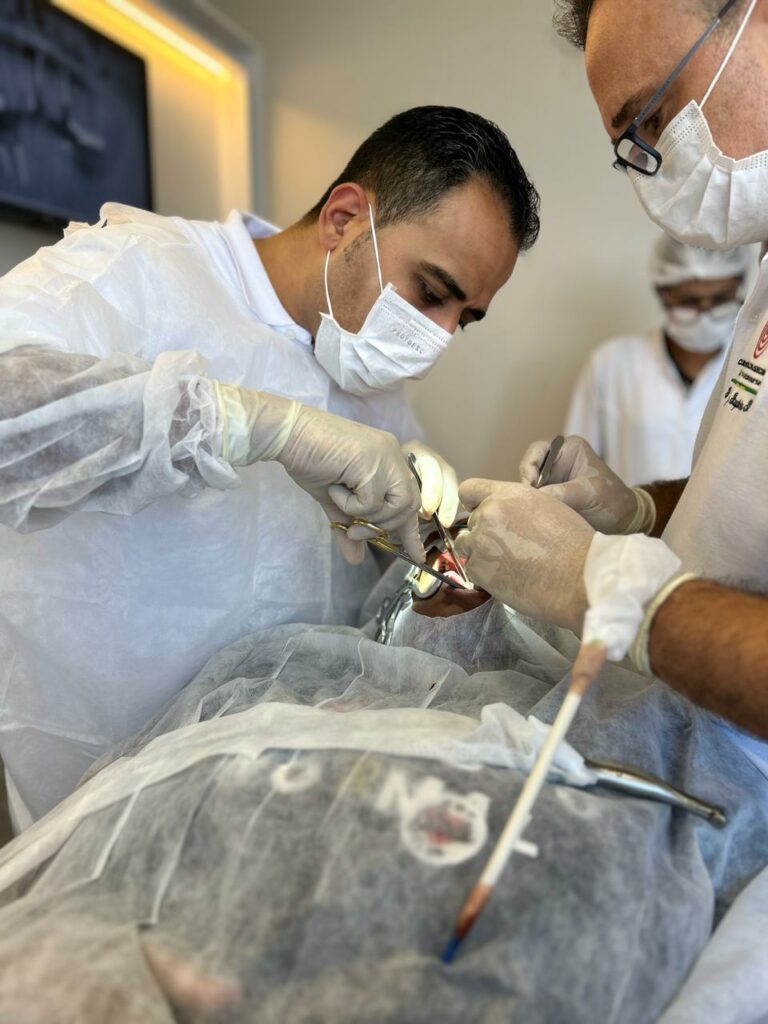

IL CORSO DI IMPLANTOLOGIA E CHIRURGIA ORALE PRATICO SU PAZIENTE IN BRASILE

ONE TO ONE

Scopri l’eccezionale opportunità formativa offerta da Cursos Internacionais de Cirurgia, il percorso ideale per chi desidera migliorare ed eccellere nella chirurgia orale e maxillo facciale

SII TU IL PRIMO OPERATORE, SEMPRE! DALL’INIZIO ALLA FINE. IL TUO ASSISTENTE SARA’ UN TUTOR DEDICATO CHE TI SEGUIRA E GUIDERA’ PASSO DOPO PASSO NELLA RISOLUZIONE DEL CASO CHIRURGICO!